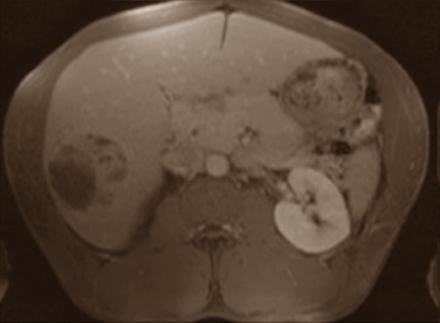

The man was 1.80 m and weighed 118 kg. He had gone to hospital because he had stomach pains, so the doctors made scans of his abdominal area. A swelling in the liver showed up in these. [The dark patch below left.]

The doctors decided to operate on the man. They removed the part of the liver where the tumour was located; the tumour itself measured 6 x 5 x 5 cm. In the lab they discovered that it was hepatocellular carcinoma that the man had developed.